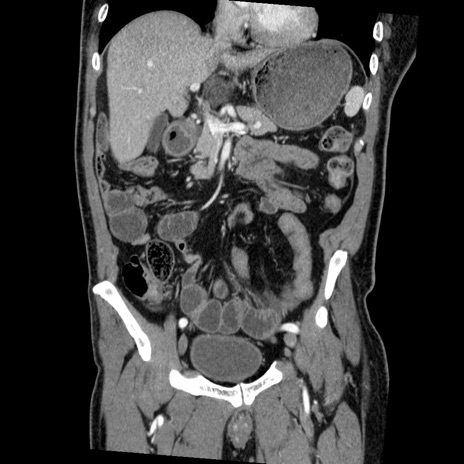

症例22(冠状断像)

【症例】50歳代男性

【主訴】腹痛

【現病歴】AVMからの被殻出血のため回復期リハ病棟入院中。 本日午後3時頃急に下腹部痛が出現した。

【既往歴】AVM、被殻出血、虫垂炎、高血圧

【身体所見】意識晴明、左半身不全麻痺、会話の理解は良好、36.5°C、腹部:膨隆、全体に板状硬、下腹部正中に圧痛点あり、反跳痛-、筋性防御不明、右下腹部にope scar

【データ】WBC 9400、CRP 0.06